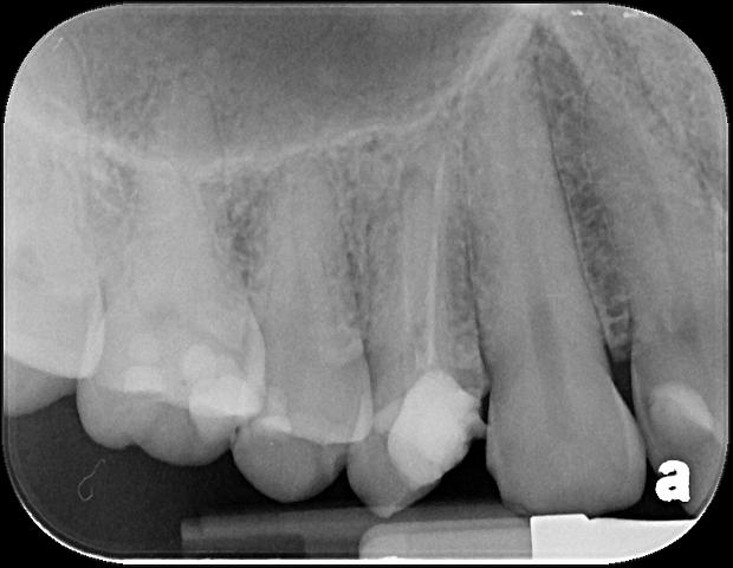

治療前,第一大臼齒根尖病變

顯微根管重治療